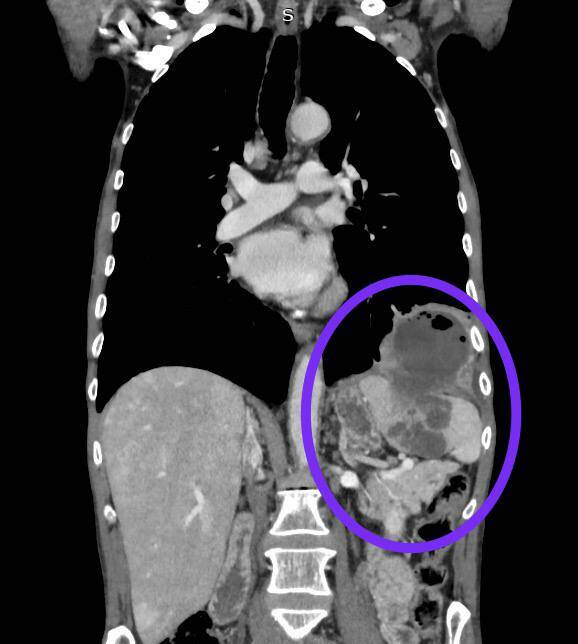

Фото: РКБ Татарстана

По словам врачей, за свою практику они впервые увидели опухоль нижней доли легкого, которая сквозь диафрагму проросла в селезенку и при этом некротизировалась.

Торакальные хирурги – специалисты РКБ, изучив клиническую картину, заподозрили злокачественный процесс. В отделении торакальной хирургии пациенту поставили предварительный диагноз – образование нижней доли легкого с распадом.